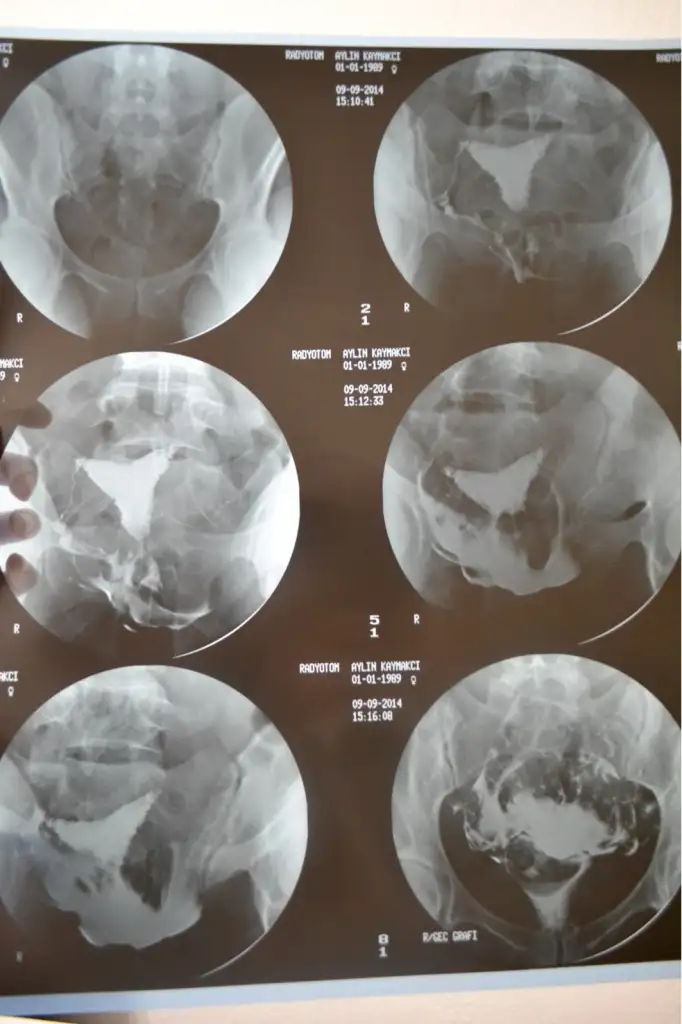

ben 2.5 yıldır bebek için tedavi görüyorum. polikistik over hastasıyım. geçen sene eylül ayında aşılama yapıldı fakat ohss gelişti hastahanede yatarak tedavi edildim. hiçbir zaman gebelik yaşamadım. adetlerim çok düzensiz. 2 ay önce doktorumu değiştirdim. klomen tedavisine başlandı ilk tedavide sağda 2 solda 1 yumurta oluştu çatlatma iğnesi yapıldı fakat birlikte olamadık. ikinci tedavide 1 yumurta gelişti çatlatma iğnesi yapıldı 4gün sonra idrar testinde gebelik çıktı. kan testi yaptırdım 25.99 2 gün sonra 13.57 4 gün sonra ise 0,75. klomen kullanmaya başladığımdan beri yani 2 aydır adetlerim düzenli hiçbir gecikme yaşamadım. doktor kimyasal gebelik dedi. daha önceden rahim filmi çektirmiştim rahim etrafı pürüzlü bakmamız lazım dedi doktor. birde siz yorumlarmısınız? teşekkürler.

Merhabalar :Rahım - tup fılmı normal gozukmekte.2.5 yıl gıbı uzun bır sure .Yumurtlatma tedavılerı yapılmıs saglıklı gebelık elde edılememıs olması ve ohss gelısmıs olması nedenı ıle ureme ıle ılgılı deneyımlı bır hekım tarafından hangı yoldan gıdılmelı karar verılmesı faydalı olucaktır.Sıze hem emnıyet ( ohss gelısmemesı ıcın ozel catlatma ıgnelerı kullanımı ve embrıo dondurulması)hem daha yuksek gebelık oranı verecek tup bebek mı ? yapılmalı ? bu konular üzerınde detaylı bılgı verılecektır.